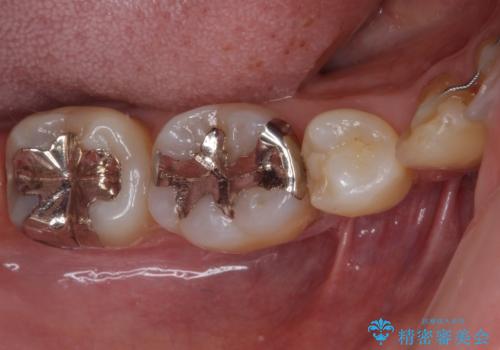

矯正治療後には、下顎臼歯の目立つ銀歯をセラミックインレーにて修復治療を行いました。

口を開けたときに金属が見えなくなり、患者様には大変満足していただきました。